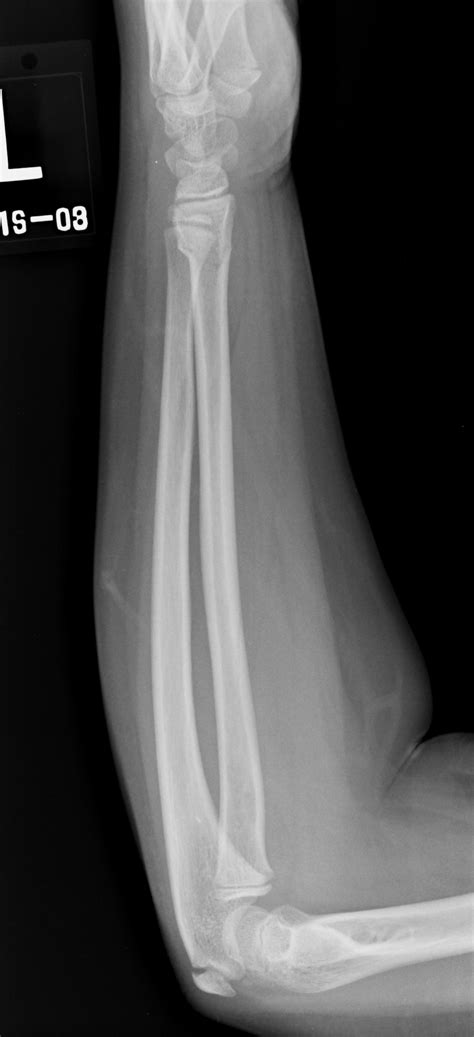

When you take a child to the emergency department for a suspected buckle fracture radius, the physician will perform a physical examination followed by an X-ray. It is important to note that because the fracture is a compression rather than a gap, it can sometimes be difficult to see on an X-ray unless the image is taken from exactly the right angle.

Radiologists look for a small "kink" or cortical disruption on the distal radius. Sometimes, a subtle thickening of the cortex is the only diagnostic clue. If the initial X-ray is inconclusive but the clinical suspicion remains high, doctors may recommend a follow-up visit or immobilization as a precautionary measure.